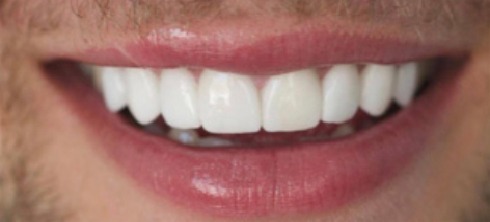

A 26-year-old female with severe crowding. Comprehensive orthodontic treatment was completed. Patients were amazed by the results.

Crowding and constricted arch. Comprehensive orthodontic treatment was performed, and teeth alignment was restored.